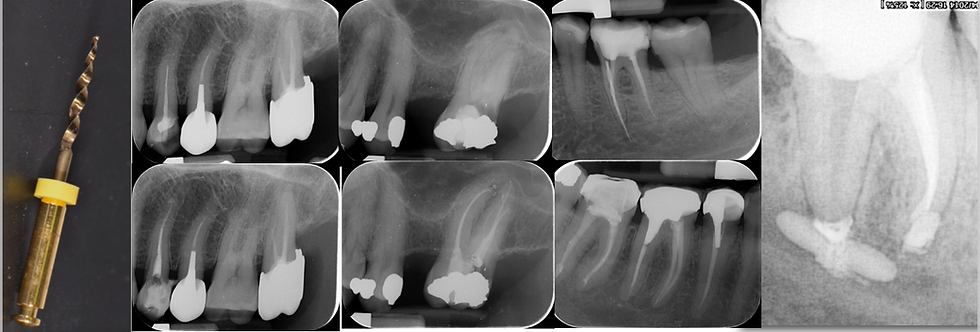

MasterClass: Gestion des échecs en endodontie

et si nos échecs nous permettaient de progresser...

Analyser vos échecs en endodontie sans culpabilité, en comprenant clairement leurs causes biologiques, techniques et cliniques.

Aborder les situations endodontiques complexes avec méthode et confiance, afin de prévenir les complications et mieux gérer celles qui surviennent.

Transformer vos échecs en leviers d’amélioration continue, en faisant évoluer votre pratique sur des bases cliniques solides et scientifiquement fondées.